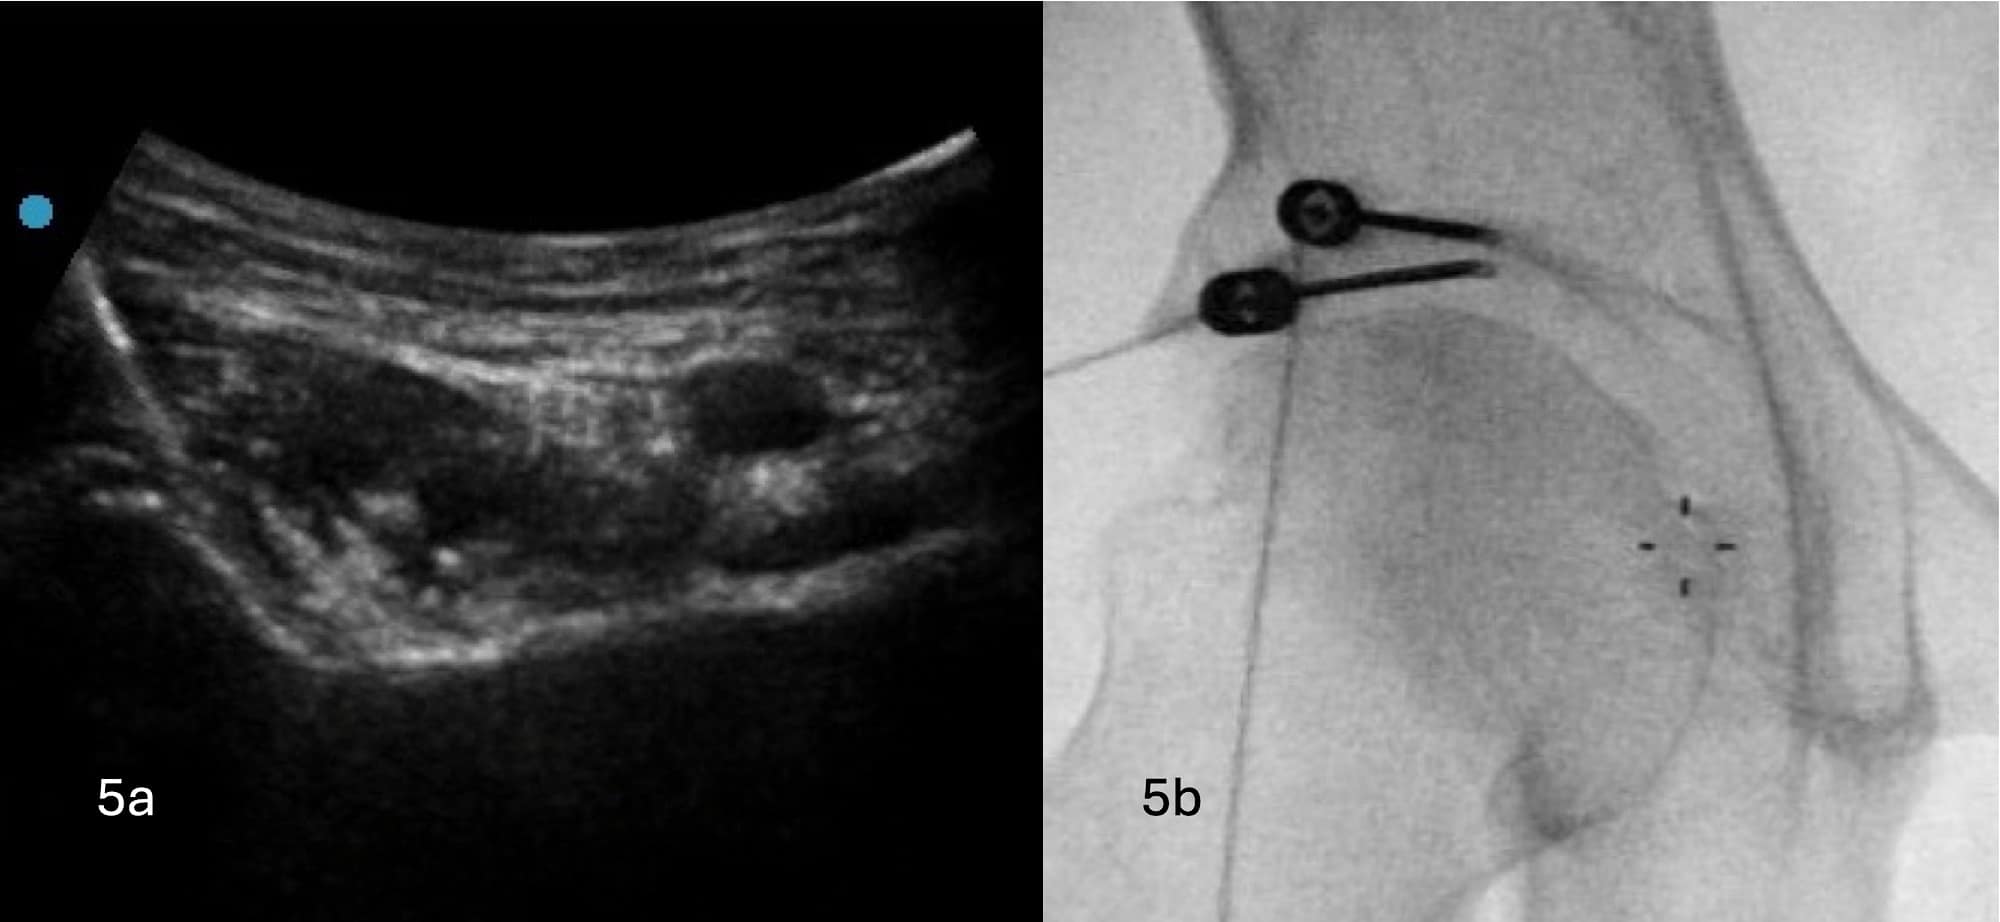

Sequential bipolar RF is carried out with the cannulas withdrawn slightly each time to ensure the entirety of the area between AIIS and IPE is covered (see Figures 5A and 5B).

Figure 5A. Ultrasound image demonstrating withdrawn RF cannula compared to Figure 4. Figure 5B. Fluoroscopic image demonstrating the corresponding position of the withdrawn RF cannula.